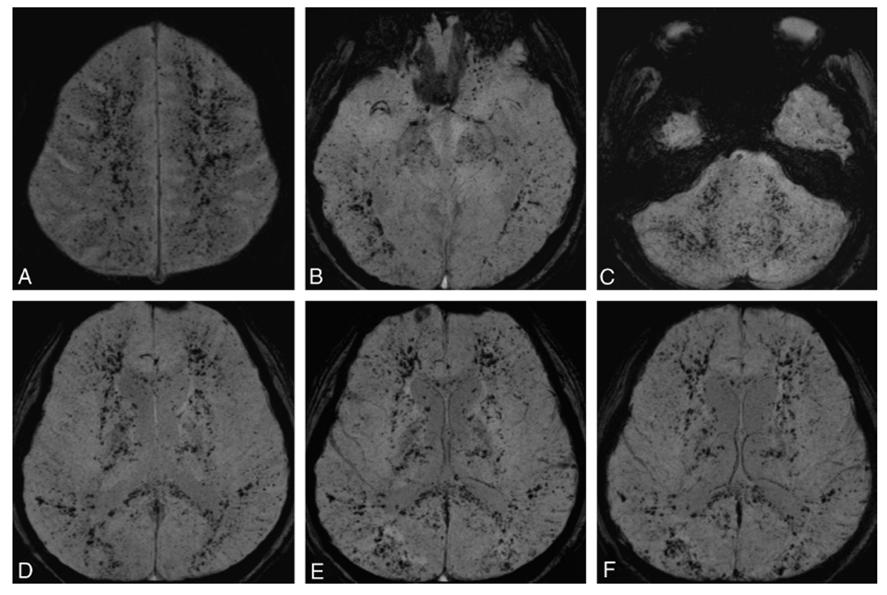

ECMO用于常规治疗无效的患者提供心脏和(或)肺支持。ECMO相关神经系统并发症多见,包括脑梗死、ICH、CMBs、脑水肿、认知功能下降和脑死亡。

ECMO幸存者CMBs呈多发、弥漫性且相对对称,位于皮层下和深部白质。

ECMO支持后 T2*WI(A, C)和SWI(B, D)示皮层下弥漫性CMBs,主要分布在皮层U形纤维。

脂肪栓塞综合征通常由长骨骨折引发,骨髓中游离的脂肪进入血液循环所致。在脂肪栓塞综合征患者中,CMBs常见且主要分布在白质(尤其是分水岭区),也可见于灰质。这些脂肪栓塞相关CMBs与DWI上小的梗死相关。

脂肪栓塞综合征 骨折3周后SWI示双侧皮层下和脑室周白质、大脑半球、大脑脚、胼胝体后部弥漫性的CMBs (A-D)。骨折5周后复查SWI同前(E-F)。